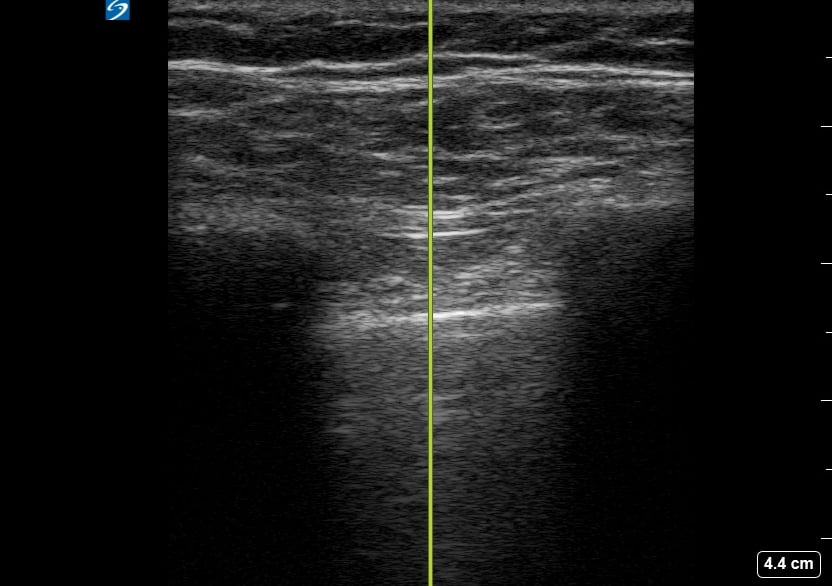

A pneumothorax, or collapsed lung, occurs when air leaks into the space between the lung and chest wall, causing the lung to partially or completely deflate. In a medical setting, prompt diagnosis is crucial to prevent respiratory distress. Ultrasound is a valuable tool for quick assessment, revealing characteristic signs like the absence of lung sliding or the presence of a “barcode” or “stratosphere” sign in M-mode, aiding rapid clinical decisions.

Ultrasound imaging for pneumothorax offers a non-invasive, real-time method for detection, especially in emergency and critical care. Key ultrasound findings guide clinicians in identifying this potentially life-threatening condition, facilitating timely intervention and improved patient outcomes. Understanding these signs is essential for medical professionals utilizing point-of-care ultrasound for lung pathology.